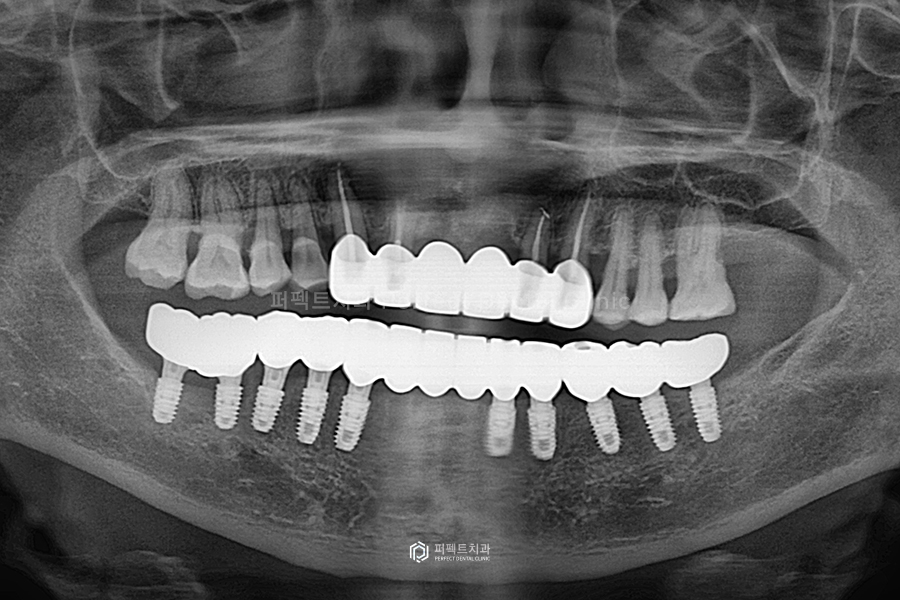

전후 사진을 보시면 교합평면 높이가 좋아지고, 전체적으로 치아가 반듯해진 것을 한 눈에 확인할 수 있습니다.

전체적으로 정리해서 말씀을 드리면 아랫니의 경우 흔들리는 앞니는 전부는 전부 발치하고, 임플란트를 10개 식립하였습니다. 윗니는 너무 흔들리는 앞니 두개만 발치를 했고, 나머지는 깨끗하게 신경치료를 한 후, 지르코니아 크라운으로 씌워서 사용하기로 하였는데요. 앞니는 걸어서 사용하는 브릿지로 완성하고 나머지는 싱글 크라운으로 하나씩 제작해서 사용할 수 있도록 해드렸습니다.

보철까지 모두 완성한 사진입니다. 굉장히 예쁘게 완성이 되었고, 환자분도 결과에 만족하셨습니다.

위 사진을 보시면 전체 신경치료 후 지르코니아 크라운을 씌웠고, 아래는 임플란트 10개를 식립 후 위에와 마찬가지로 지르코니아 크라운으로 완성을 했습니다.